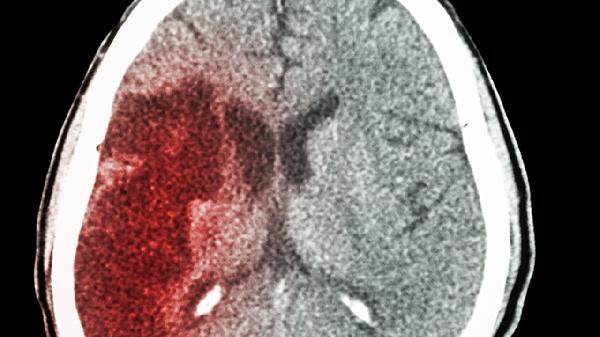

抗磷脂抗體綜合征可導(dǎo)致腦梗死或腦出血,患者突發(fā)偏癱、失語等局灶體征。急診需進行頭顱CT鑒別,治療包括阿司匹林腸溶片抗血小板、低分子肝素鈣注射液抗凝,同時加強甲氨蝶呤注射液免疫抑制。